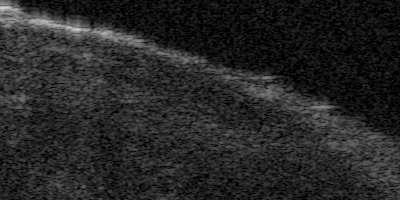

Coronary artery disease (CAD) is a cardiovascular condition with high morbidity and mortality. Intravascular optical coherence tomography (IVOCT) has been considered as an optimal imagining system for the diagnosis and treatment of CAD. Constrained by Nyquist theorem, dense sampling in IVOCT attains high resolving power to delineate cellular structures/ features. There is a trade-off between high spatial resolution and fast scanning rate for coronary imaging. In this paper, we propose a viable spectral-spatial acquisition method that down-scales the sampling process in both spectral and spatial domain while maintaining high quality in image reconstruction. The down-scaling schedule boosts data acquisition speed without any hardware modifications. Additionally, we propose a unified multi-scale reconstruction framework, namely Multiscale- Spectral-Spatial-Magnification Network (MSSMN), to resolve highly down-scaled (compressed) OCT images with flexible magnification factors. We incorporate the proposed methods into Spectral Domain OCT (SD-OCT) imaging of human coronary samples with clinical features such as stent and calcified lesions. Our experimental results demonstrate that spectral-spatial downscaled data can be better reconstructed than data that is downscaled solely in either spectral or spatial domain. Moreover, we observe better reconstruction performance using MSSMN than using existing reconstruction methods. Our acquisition method and multi-scale reconstruction framework, in combination, may allow faster SD-OCT inspection with high resolution during coronary intervention.